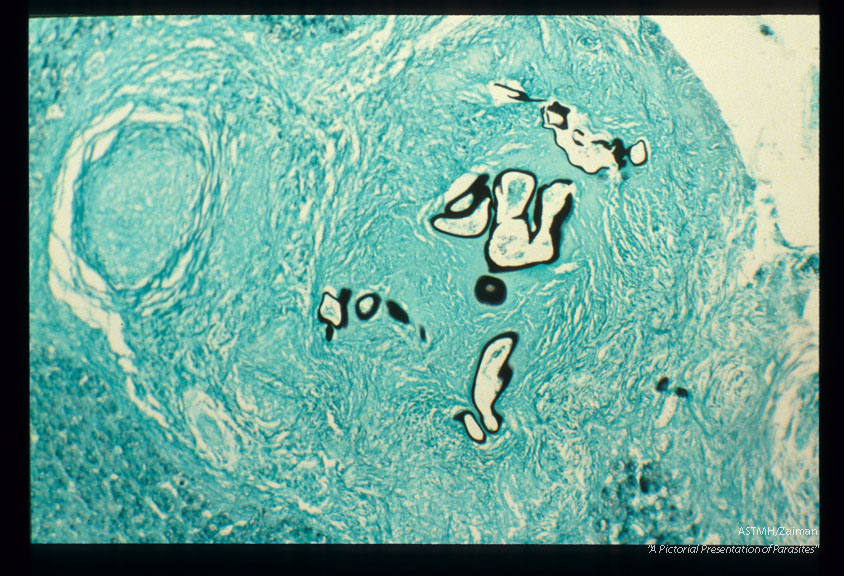

Gross and microscopic photos of human liver from Minnesota where about one half of the red foxes are infected.

Echinococcus multilocularis

Description: Gross and microscopic photos of human liver from Minnesota where about one half of the red foxes are infected.